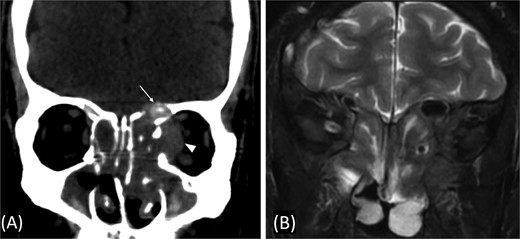

A 31-year-old man, who is a known case of Gilbert syndrome, presented to the rhinology clinic with a 1-year history of progressive bilateral nasal obstruction and left eye proptosis. The patient had previously undergone FESS twice outside the hospital for allergic fungal rhinosinusitis, with the most recent procedure having been performed two years before his presentation at the clinic. On examination, the nasal endoscopy showed extensive nasal polyposis, while the neurological examinations were normal. The CT scan and MRI revealed a mass in the left ethmoid cavity with an erosion of the lamina papyracea, extending into the extraconal fat and obstructing the frontal recess with mucosal thickening (Fig. 3). The patient was therefore suspected of having recurrent fungal rhinosinusitis and underwent FESS for debulking and to obtain a biopsy. Postoperatively, the histopathological results confirmed the diagnosis of CGIFRS, and A. flavus was found in the tissue culture. The patient was then started on oral voriconazole for 3 months.

Paranasal CT scan without contrast a mass in the left ethmoid cavity with erosion of the lamina papyracea (arrow).